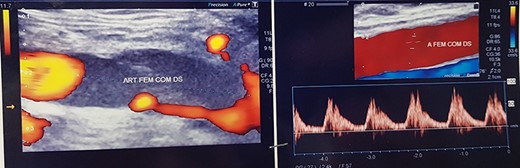

Duplex ultrasound examination (DUS, Fig. 1) showed a segmental sub-occlusive hypoechoic stenosis of the anterior wall of the right CFA.

The intraoperative completion DUS showed the patency of the CFA and of the femoro-popliteal axis with triphasic flow maintained until tibial vessels (Fig. 4).